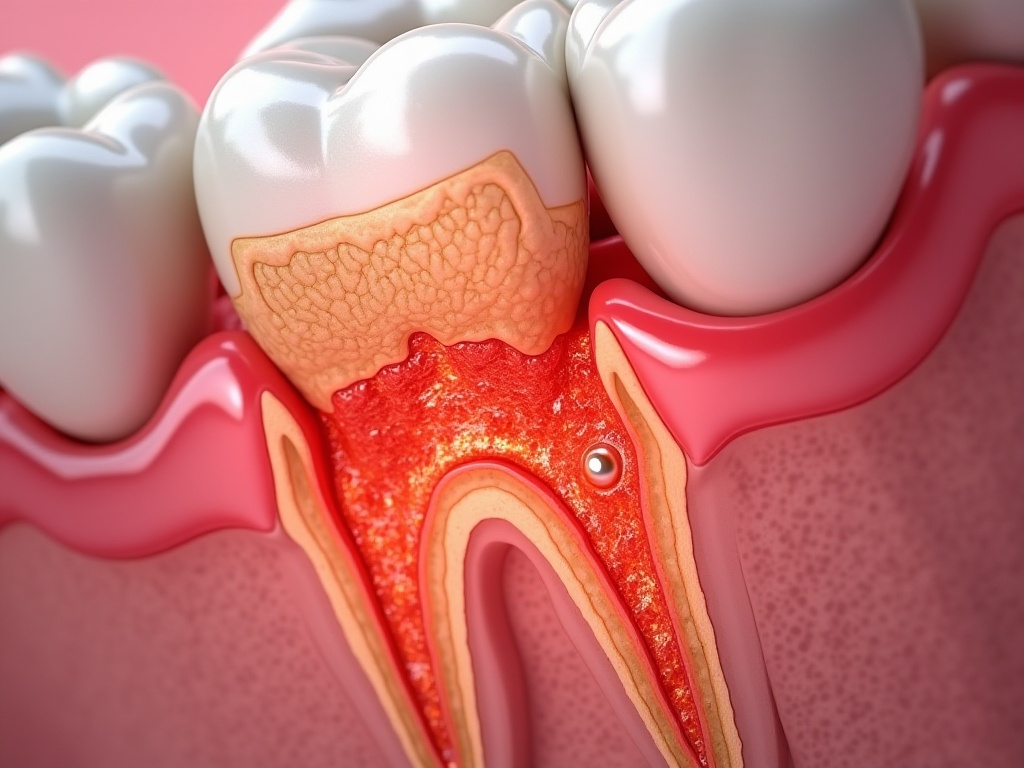

사랑니로 인해 잇몸이 붓고 충치가 생깁니다.

염증이나 충치가 있는 사랑니를 방치하면 인접한 큰 어금니 혹은 사랑니 주변 잇몸뼈에 문제를 일으킵니다. 아플 때까지 방치 했다면 이미 주변에 많은 문제를 일으킬 가능성이 높습니다. 관리가 어려운 사랑니는 미리 뽑으시는 것이 좋습니다.

칫솔이 닿지 않는 부위로 인해 사랑니가 부패된다.

사랑니와 인접한 어금니 사이에 음식물이 자주 낀다. 잔여 음식물이 사랑니 주변 치아까지 부패시키는 원인이 된다.

사랑니 주변 잇몸에 염증이 발생하며 잇몸과 볼이 붓게 됩니다.

염증이 심한 경우 낭종, 종양, 골수염 등의 문제를 일으킬 수 있습니다.